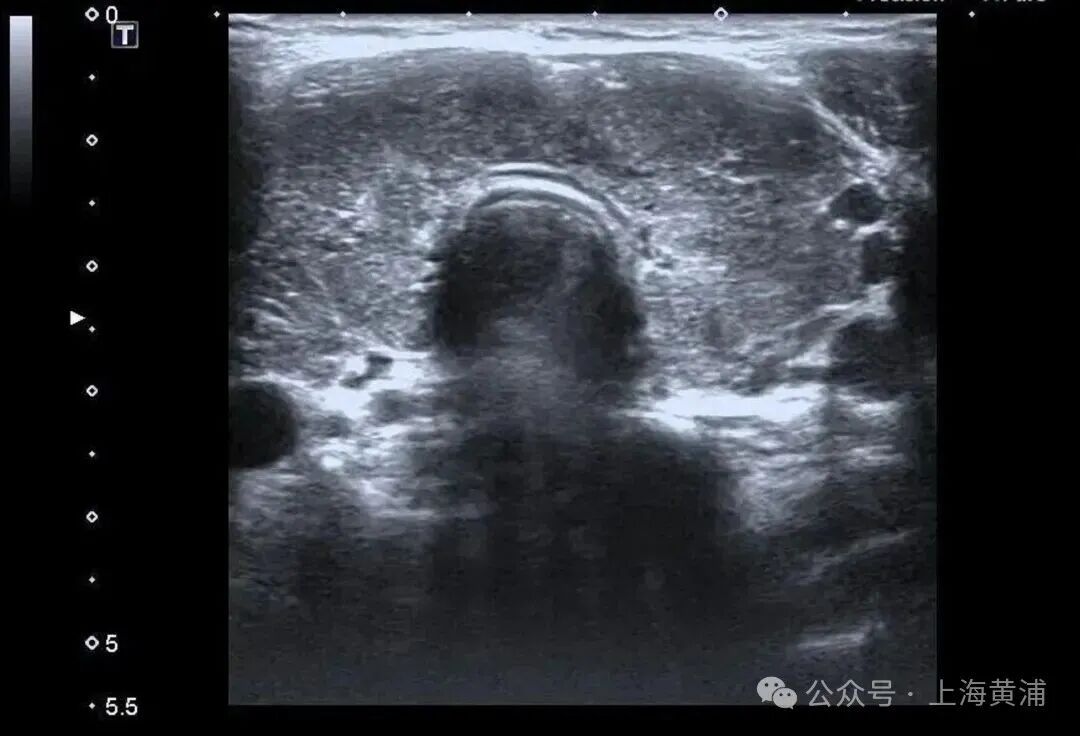

{jz:field.toptypename/}甲状腺功能查验中,游离T3高达20.83 pmol/L(正常值3.5 - 6.5pmol/L),游离T4高达88.42 pmol/L(正常值11.5 - 22.7pmol/L),这两项中枢激素都杰出正常上限数倍,而本应调控它们的促甲状腺激素(TSH)却险些测不出来,这明确说明了陈女士患有极其严重的甲状腺毒症。腹黑超声终结通常笼罩乐不雅,射血分数仅有40%(正常应高于55%),这意味着腹黑泵血才略大幅着落。

同期,CT查验发现她的双侧胸腔、腹腔存在积液。抽象各项查验终结,医师判断陈女士患上了甲状腺危象,这是甲亢最不吉的并发症。